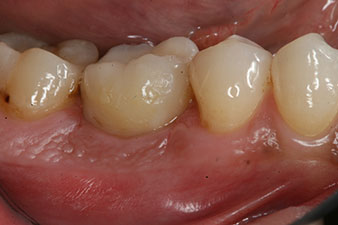

The final pictures show the screw-retained monolithic composite crown in place and the x-ray check (Fig. 9 and 10) (6).

composite crown

Fig. 9: The final composite crown was cemented on a PEEK hybrid abutment in the laboratory and can be screwed in place immediately.

x-ray check

Fig. 10: The x-ray check shows the success of the osseointegration and the crown screwed in position without a gap.